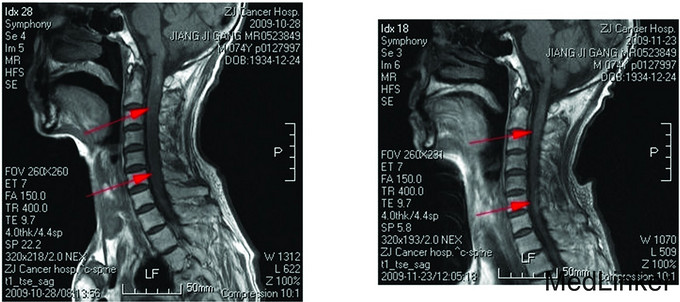

Cerebellar brainstem and spinal cord metastasis from esophageal cancer after radiotherapy is very rare. Here we report a case of a 74-year old male who was admitted to hospital with a poorly differentiated neuroendocrine carcinoma of the esophagus. After radiotherapy, multiple abnormal signals in the brainstem and spinal cord were found on magnetic resonance imaging (MRI). After treatment, clinical symptoms and abnormal MRI signals in the brainstem and spinal cord improved. This case revealed that brain metastasis from esophageal carcinoma may occur simultaneously with brainstem and spinal cord metastases.